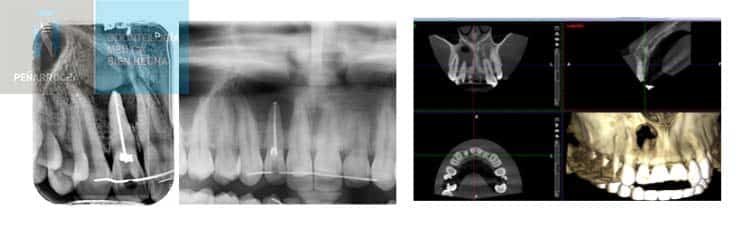

El especialista analizará el motivo de tu visita, por ejemplo, una endodoncia fracasada y los síntomas. Revisará tu historial y las radiografías para confirmar o reevaluar el diagnóstico inicial.

En algunos casos, será necesario realizar una nueva exploración o repetir pruebas como una radiografía 3D para obtener una visión más clara del estado real del diente afectado.